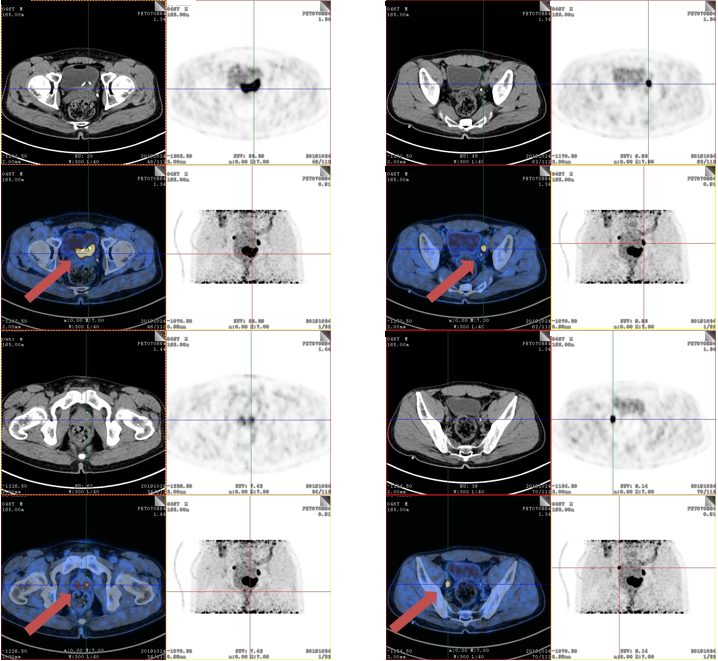

2020-2复查PET-CT提示(图4),膀胱癌综合治疗后,双侧输尿管入膀胱处FDG代谢增高,考虑肿瘤活性残留可能,较前次检查(2019-10-24)膀胱壁病灶明显缩小,右侧髂血管旁转移淋巴结体积减小、FDG代谢减低,原左侧髂血管旁淋巴结基本消失。

图4. NACI 4疗程后影像学评估

核医学科:结合NACI前后PET-CT检查结果,患者达到影像学PR(ycT1N1M0)。